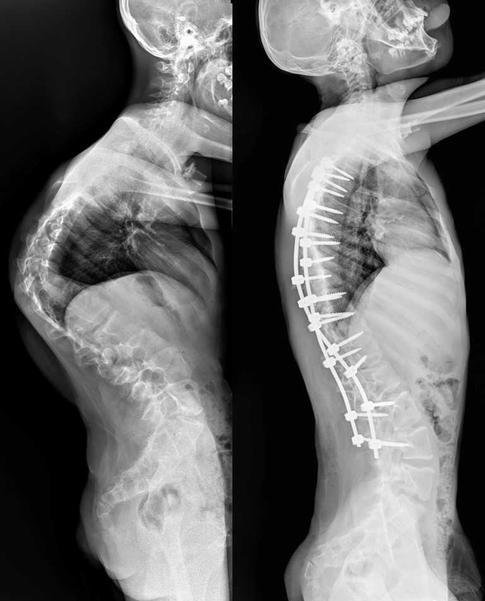

13-летний Мурат страдал от редчайшего генетического заболевания. Врачи провели ему операцию, которая длилась более семи часов. Как отмечают медики, кифотическая деформация грудного отдела позвоночника у юноши составляла более 110 градусов, а комбинированная сколиотическая — по 90 градусов в грудном и поясничном отделах.

В результате операции качество жизни Мурата значительно улучшится. Врачи говорят, что он сможет даже заниматься своим любимым делом — кататься на велосипеде. Болезнь обострилась у юноши около двух лет назад. Он поступил в больницу с существенным искривлением позвоночника.